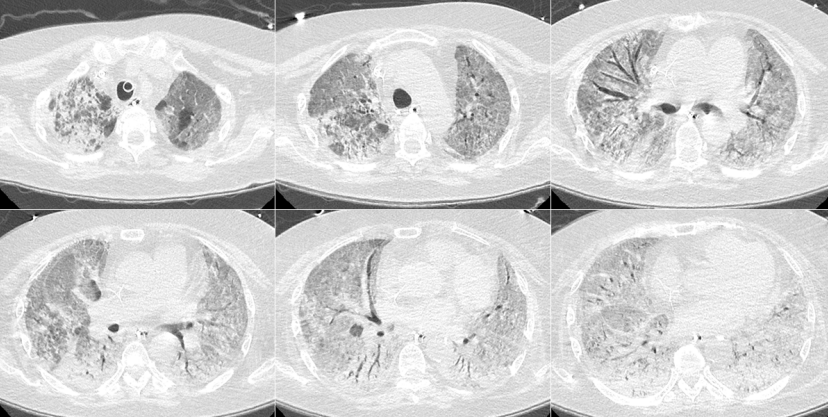

58岁男性患者,糖尿病病史,由于病情较重,2022年12月23日(起病14 d)胸部CT如下图所示。

患者2022年12月23日胸部CT

图片

予地塞米松10 mg qd,同时予巴瑞替和托珠单抗治疗,患者CRP明显下降。1月4日因患者循环不稳,担心管路相关血流感染引起感染性休克,撤离ECMO。在ECMO期间,患者临床指标和氧合均得到明显改善,影像学明显吸收。

患者胸部CT变化情况

1月9日4:00患者血压下降[60/40 mmHg,去甲肾上腺素1.4 μg/(kg·min)],心率120~130次/min,PFR由200 mmHg降至106 mmHg。调整治疗策略:更换PICC、动脉/拔除血滤管,多黏菌素+替加环素+阿米卡星+万古霉素抗感染,补液:2023年1月9日和10日共补液11000 ml,去甲肾上腺素剂量由1.4下调至1.0 μg/(kg·min)。1月10日胸部CT示:肺内渗出增多,符合COVID-19特点。

患者2023年1月10日胸部CT

2023年1月10日BALF NGS阴性,WBC/PCT无继续升高,新冠核酸CT值35,IL-6 3090 pg/ml。予甲强龙(80 mg qd)联合托珠单抗治疗,去甲肾上腺素逐渐减量,至1月13日停用,1月16日患者影像学明显改善。

患者2023年1月16日胸部CT